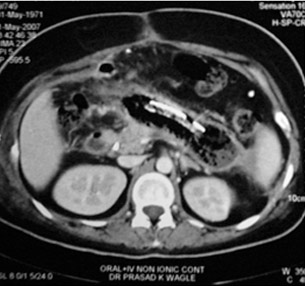

CT scan of Chronic pancreatitis with cancer (stent seen in the pancreatic duct, arrow pointing the tumor)

CT scan of chronic pancreatitis with large tumor, stones in the pancreatic duct